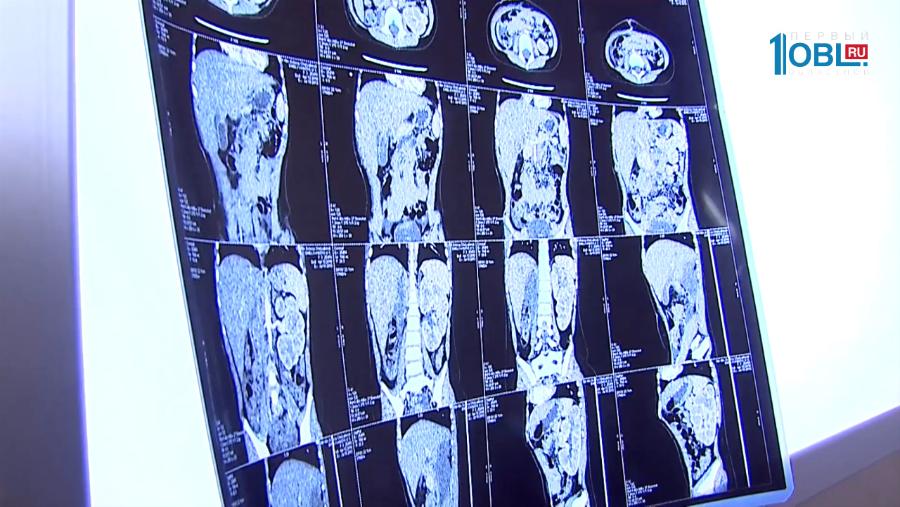

Не режет, а лечит. Современное оружие в борьбе с онкологическими заболеваниями. Кибернож объединил в себе достижения робототехники, компьютерной навигации и лучевой терапии. Что делает его максимально точным? И почему он так и не стал панацеей от всех разновидностей рака?